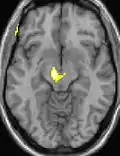

Voxel-based morphometry shows brain area structural differences.

Positron emission tomography (PET) scans indicate the brain areas which are activated during attack only, compared to pain free periods. These pictures show brain areas that are active during pain in yellow/orange color (called "pain matrix"). The area in the center (in all three views) is activated only during cluster headaches. The bottom row voxel-based morphometry shows structural brain differences between individuals with and without CH; only a portion of the hypothalamus is different.[36]